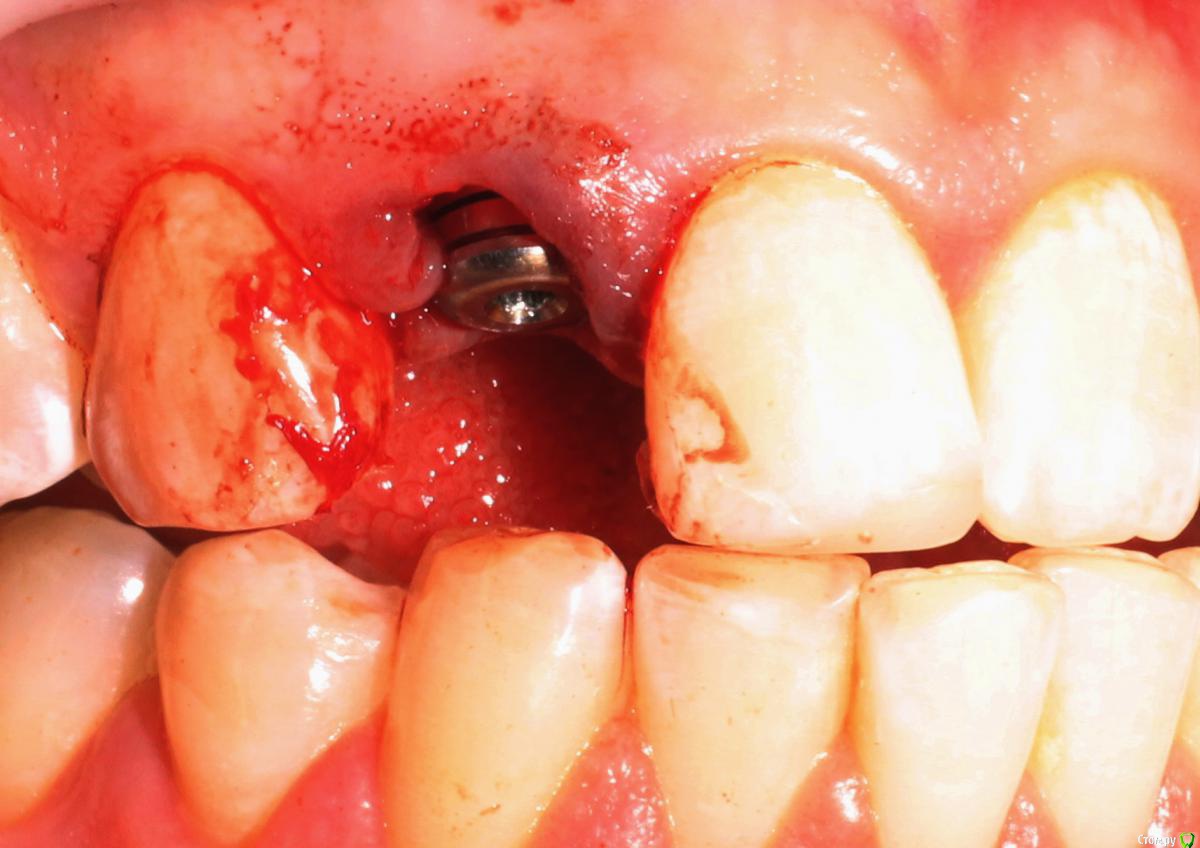

MenshikovDV Опубликовано 2 апреля, 2015 Поделиться Опубликовано 2 апреля, 2015 (изменено) Зуб 1.2 отлом коронковой части зуба, на период ожидания приема у хирурга и ортопеда (2 дня) приклеен к соседям. Вся процедура в одно посещение. Где-то часа два. Я ортопед, хирургия не моя, фото мои Изменено 2 апреля, 2015 пользователем MenshikovDV 19 Ссылка на комментарий

Aquarius Опубликовано 5 апреля, 2015 Поделиться Опубликовано 5 апреля, 2015 в такую дыру лучше что-нибудь кинуть, имхо. Ссылка на комментарий

Alexey Doc Опубликовано 5 апреля, 2015 Поделиться Опубликовано 5 апреля, 2015 Класс! Аккуратно сработали!Единственно, думаю что аугментации была бы желательна. Ссылка на комментарий